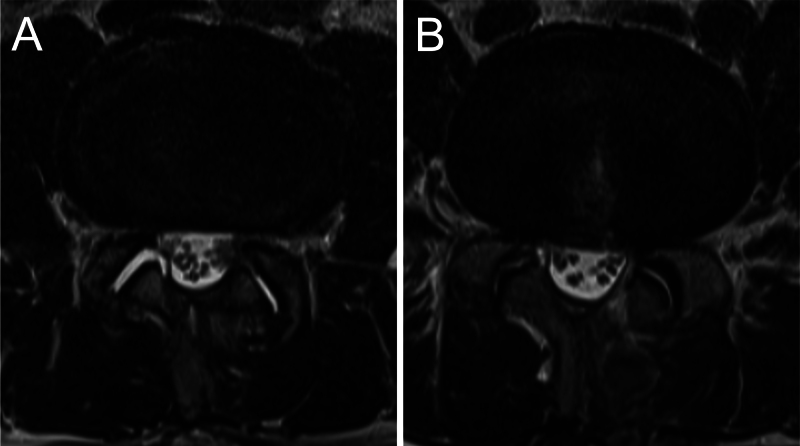

Observations: A 60-year-old man underwent UBE decompression for lumbar canal stenosis and experienced immediate symptom relief. However, 3 weeks postoperatively, he developed acute severe radicular pain, initially presumed to be caused by disc herniation. Despite repeated decompression, his symptoms progressively worsened. MRI findings remained nonspecific, without CSF leakage. Exploratory surgery ultimately revealed herniation of the cauda equina through an occult dural tear. Surgical repair led to rapid symptom relief and complete recovery without neurological deficits.

Abstract Image